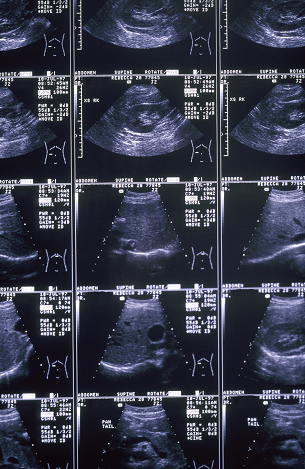

젊은 미혼 여성들에게 조차 흔히 발견 될 수 있는 자궁근종, 얼마 전 건강검진을 받은 30대 초반 정00씨는 자궁근종이 발견 되어 자궁적출수술을 권유받았다. 생각지도 못했던 병명과 함께 자궁적출수술을 해야 한다는 사실이 정00씨에게는 큰 충격으로 다가왔기 때문에 정씨는 선뜻 수술을 하는 것이 내키지 않았다.

결과적으로 정씨는 자궁적출수술 없이 한방치료만으로 자궁근종을 완치할 수 있었다. 이처럼 자궁 적출 수술 없이 한방치료로 자궁근종을 치료 하는 여성들이 많아지고 있다.